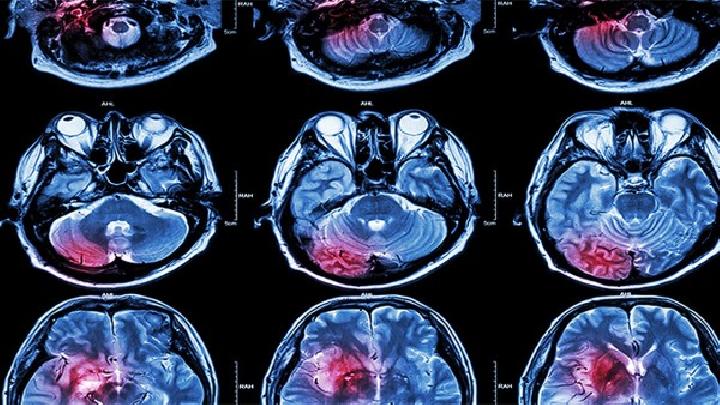

脑瘫手术治疗是一种不错的治疗脑瘫方法,选择的人也有很多,脑瘫手术治疗可以有效的改善畸形,下面脑瘫专家为大家介绍下小儿先天性脑瘫康复治疗有关内容,希望可以帮助大家。

一些年龄比较大的脑瘫患者肌肉痉挛明显,长期的肌肉痉挛常导致了,仅靠康复训练不能有效改善肢体畸形,如果不进行手术治疗,康复治疗也不会获得很好的效果。脑瘫手术治疗术式包括选择性脊神经后跟切断术、颈总动脉周围交感神经网部分剥脱切除术、肌腱延长术、骨科矫形术、内收肌切除术、闭孔神经前枝切断术等。

对于5岁以上的智力正常的痉挛性脑瘫患儿,可以进行选择性脊神经后跟切断手术,手术可显着减轻脑瘫儿肢体痉挛,配合术前术后的功能锻炼,效果较好。

颈总动脉周围交感神经网部分剥脱切除术可以增加脑血流量,可以改善痉挛状态,对部分患者的流涎、斜视、吐字不清、共济失调等症状也有一定的作用,一般应用于1~5岁的混合型脑瘫患儿。

肌腱延长术可有效改善患儿足跟不能着地的状态,有利于站立和行走的训练。而对于严重的骨骼畸形,需要应用骨科矫形术进行矫形。内收肌切除术是针对脑瘫患儿内收肌群张力增高导致肢体交叉。闭孔神经前枝切断术可减轻下肢肌肉的痉挛,恢复下肢功能。